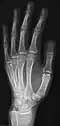

• Hand - DP and Oblique

• Fingers - DP and Lateral

• Thumb - AP and Lateral